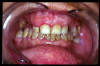

CM Caries y enfermedad periodontal avanzada